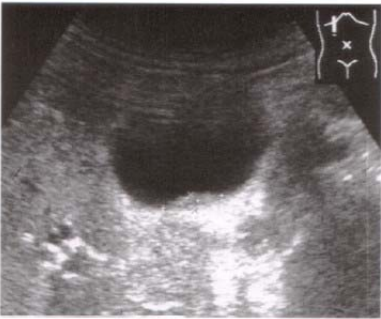

65.下圖為肝臟超音波影像,下列關於編號14號的敘述何者最正確?

(A)肝血管瘤 (B)產氣性肝膿瘍 (C)原發性肝癌 (D)膽囊